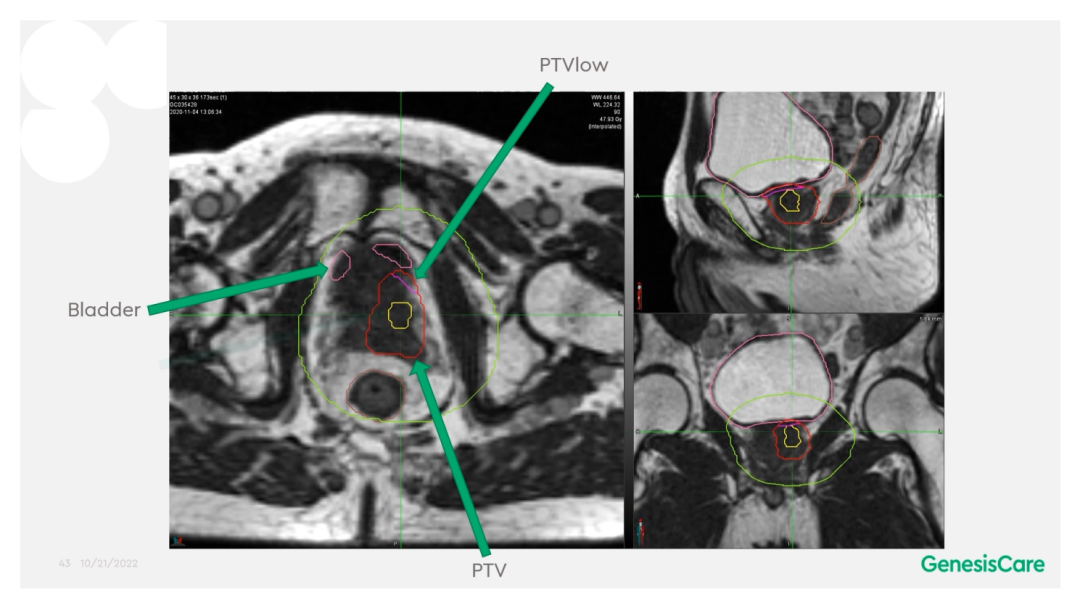

Dr. CamilleriÌåÏÖ£¬£¬£¬£¬£¬£¬ËûÃÇÔÚ×öÔÚÏß×Ô˳Ӧ·ÅÁƵÄʱ¼ä£¬£¬£¬£¬£¬£¬ÎªÁËÌá¸ßËÙÂÊ£¬£¬£¬£¬£¬£¬½ö¶Ô°ÐÇøÍâ·Å3cmÒÔÄÚµÄΣ¼°Æ÷¹ÙµÄת±ä¾ÙÐÐ×Ô˳Ӧµ÷½â»òÖØÐ¹´»ÂÖÀª£¬£¬£¬£¬£¬£¬¼ûFigure 13¡£¡£¡£¡£¡£¡£¡£ÕâÑù¿ÉÒÔËõ¶ÌÂÖÀª¹´»µÄʱ¼ä¡£¡£¡£¡£¡£¡£¡£¹ØÓÚ·ÅÁÆÍýÏ룬£¬£¬£¬£¬£¬Ê¹µÃ95%µÄ°ÐÇøÌå»ý½ÓÊܵ½100%µÄ´¦·½¼ÁÁ¿ÁýÕÖ£¬£¬£¬£¬£¬£¬²¢½«×î´ó¼ÁÁ¿ÏÞÖÆÎª2%µÄ°ÐÇøÌå»ý²»Áè¼Ý´¦·½¼ÁÁ¿µÄ110%£¬£¬£¬£¬£¬£¬ÕâÑù¾ÍÄܰü¹ÜÔÚͼÏñÉϺÜÄÑÏÔʾµÄÄòµÀ²»»á³¬Á¿£¬£¬£¬£¬£¬£¬¼ûFigure 14¡£¡£¡£¡£¡£¡£¡£ÁíÍ⣬£¬£¬£¬£¬£¬ÔÚÖÆ×÷·ÅÁÆÍýÏëʱ£¬£¬£¬£¬£¬£¬½«PTV·ÖΪPTV LOWºÍPTV High£¬£¬£¬£¬£¬£¬PTVºÍΣ¼°Æ÷¹ÙÖØµþµÄ²¿·ÖΪPTV LOW£¬£¬£¬£¬£¬£¬½«PTV LOWµÄ¼ÁÁ¿Ä¿µÄÉ趨ÔÚΣ¼°Æ÷¹ÙµÄÄÍÊܼÁÁ¿ÒÔÏ£¬£¬£¬£¬£¬£¬ÕâÑù¾ÍÄܰü¹ÜΣ¼°Æ÷¹Ù²»³¬Á¿£¬£¬£¬£¬£¬£¬¼ûFigure 15¡£¡£¡£¡£¡£¡£¡£